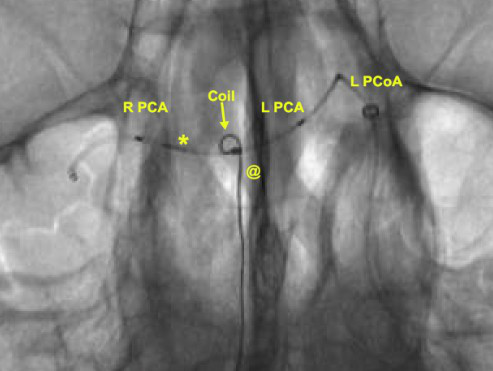

椎动脉造影(放大图像)示一个微导管(*)从左侧ICA通过左侧PCoA,经动脉瘤颈进入左侧PCA,并终止于右侧PCA远端。第二个微导管(@)位于动脉瘤中。

椎动脉造影(放大图像)示弹簧圈位于动脉瘤内,支架横跨瘤颈支撑弹簧圈。